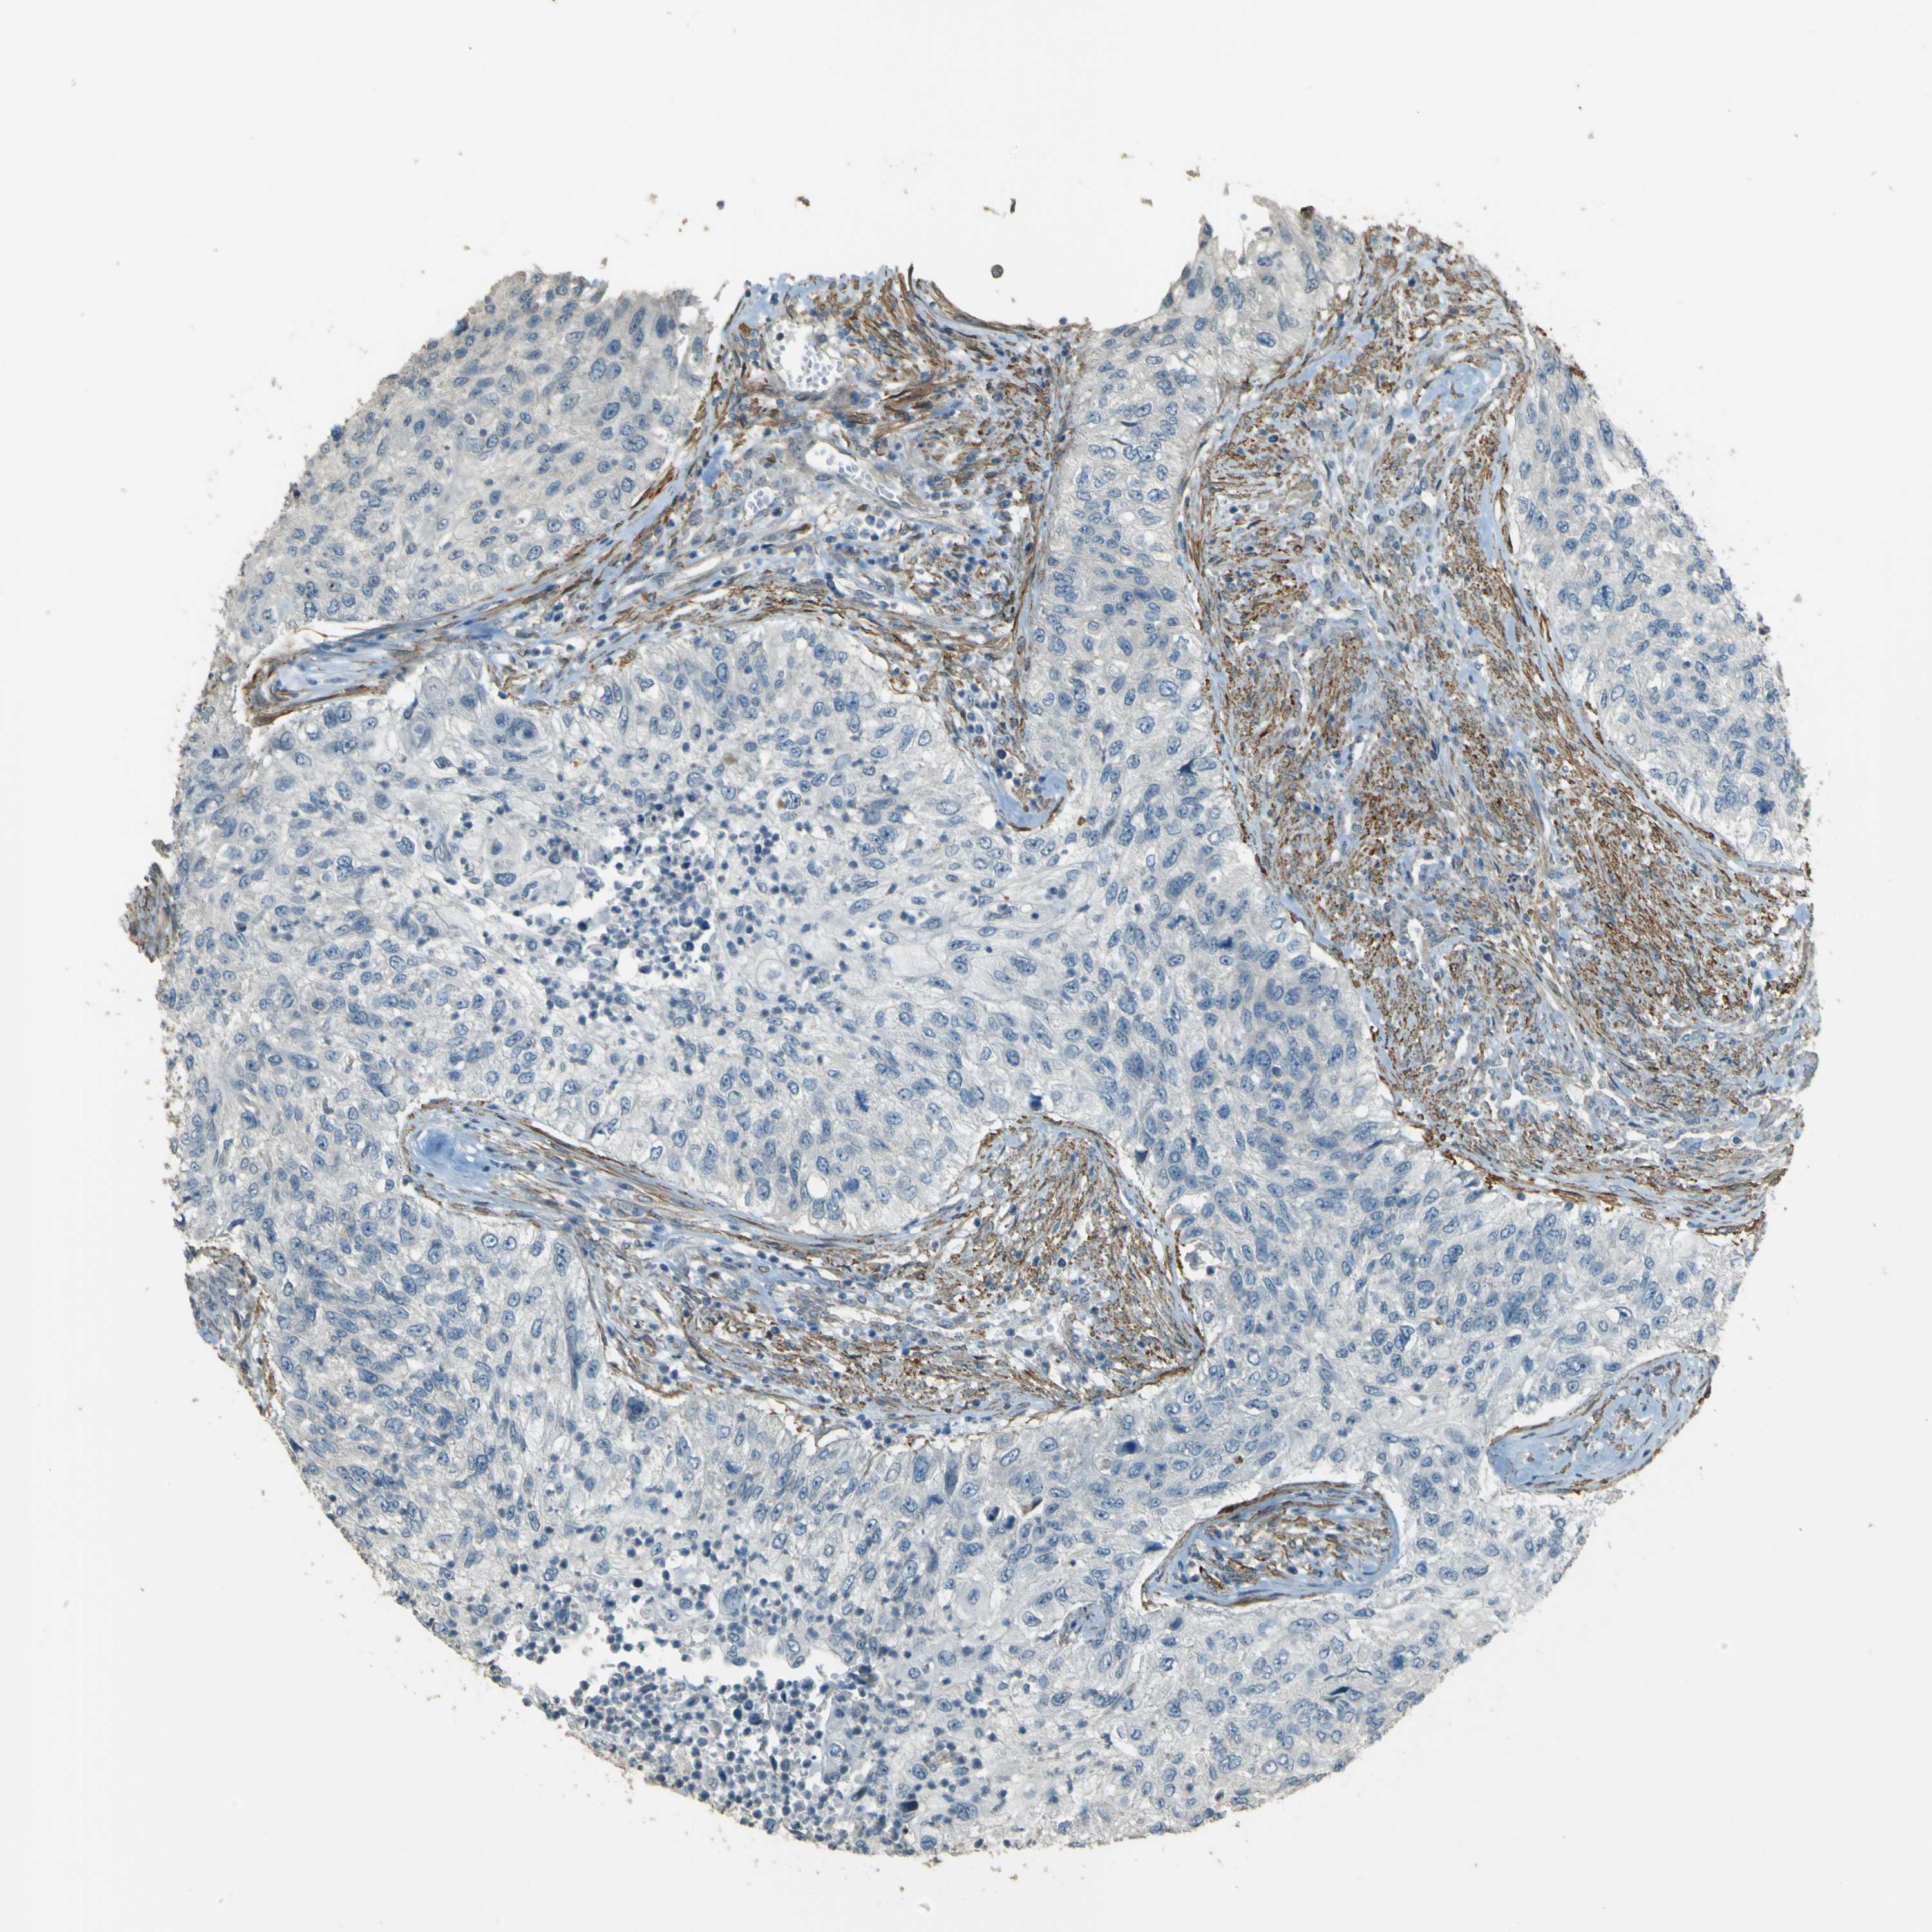

UROTHELIAL CANCER - Protein expressioni

A mouse-over function shows sample information and annotation data. Click on an image to view it in a full screen mode. Samples can be filtered based on level of antibody staining by selecting one or several of the following categories: high, medium, low and not detected. The assay and annotation is described here.

Note that samples used for immunohistochemistry by the Human Protein Atlas do not correspond to samples in the TCGA dataset.

Antibody stainingi

Antibody staining in the annotated cell types in the current human tissue is reported as not detected, low, medium, or high, based on conventional immunohistochemistry profiling in selected tissues. This score is based on the combination of the staining intensity and fraction of stained cells.

Each image is clickable and will lead to virtual microscopy that enables deeper exploration of all samples and also displays staining intensity scores, fraction scores and subcellular localization as well as patient and tissue information for each sample.

Antibody HPA011185

Staining

High

Medium

Low

Not detected

Intensity

Strong

Moderate

Weak

Negative

Quantity

>75%

75%-25%

<25%

None

Location

Urothelial carcinoma, Low grade

Urothelial carcinoma, High grade